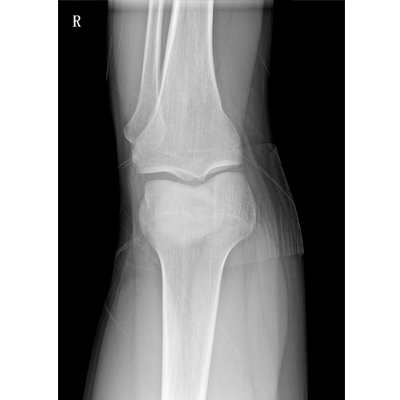

● 數(shù)字化無(wú)線平板成像,操作簡(jiǎn)便,成像質(zhì)量高